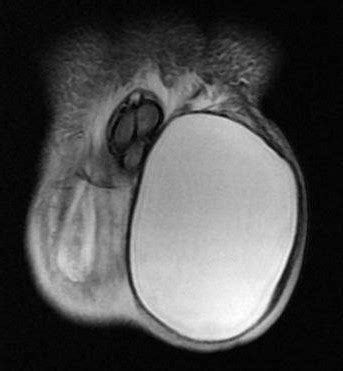

需要根据具体病情,一般在1岁之内不考虑手术,婴幼儿睾丸鞘膜积液是由于腹鞘膜突在出生前后未能闭合而形成的一个鞘膜腔,它导致液体的积聚、扩张而形成梨形的腔囊。